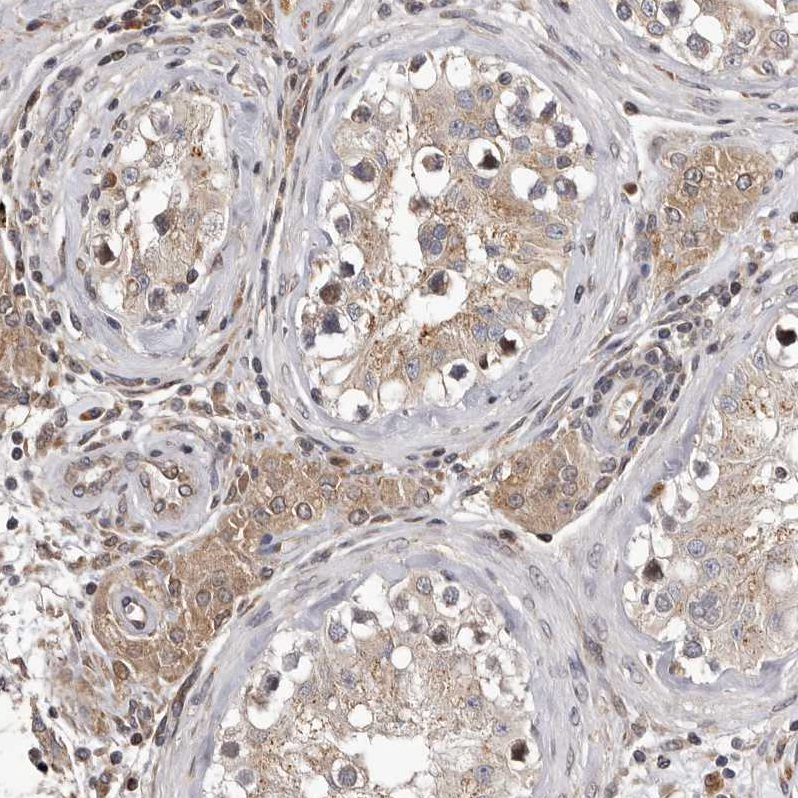

Immunohistochemical staining of human placenta shows strong cytoplasmic positivity in trophoblastic cells.